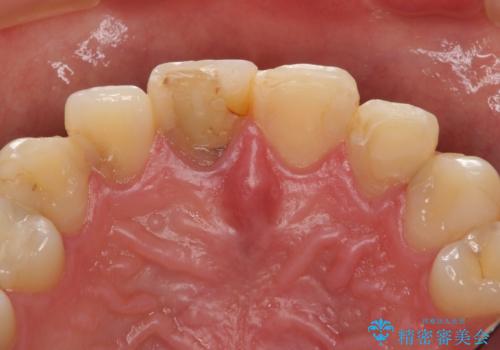

- 憧れの芸能人(ヴィジュアル系バンドマン)のような歯になりたいとのご希望で来院された患者様です。

咬み合わせが悪く矯正も検討されていたそうですが、歯を真っ白にしたいというご希望もあり、28本のすべての歯をセラミックにしたいとのことでした。

精査したところ、ほとんどの歯が保険内のレジンで充填されており、咬み合わせも悪く咬合していない歯もありました。